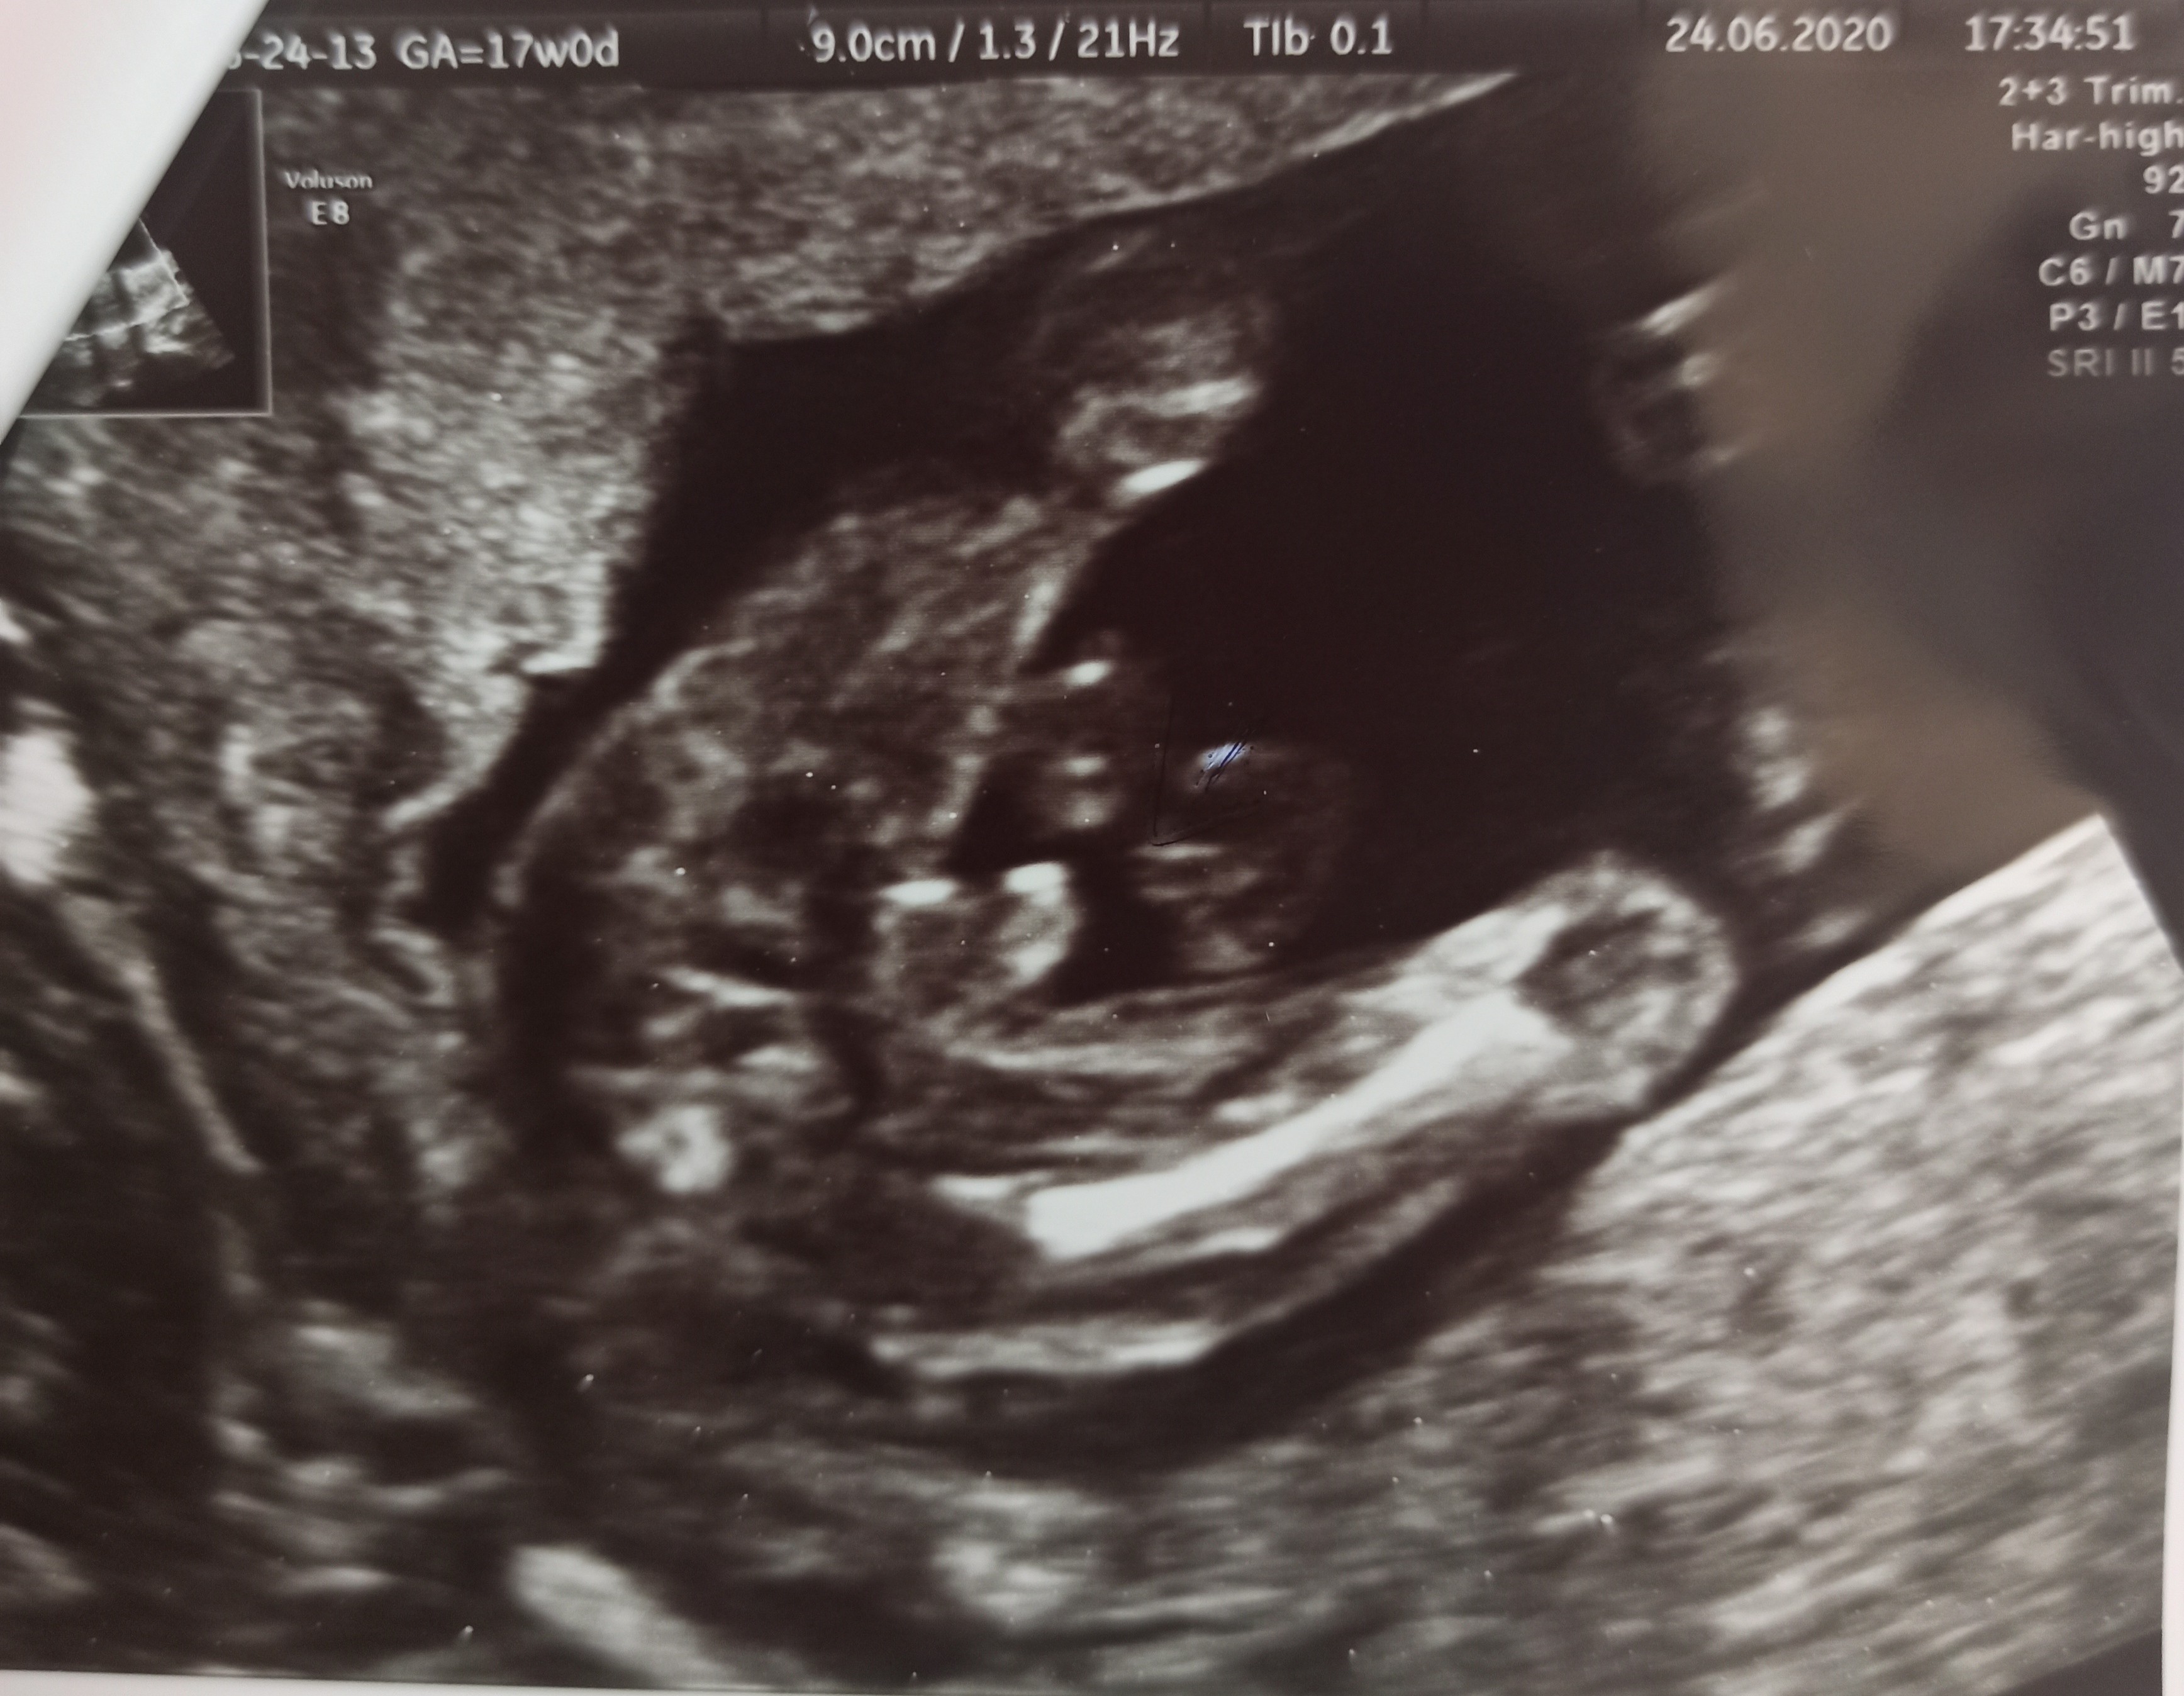

Usg chłopak czy dziewczynka

Witam w 19 tygodniu ciąży dowiedziałam się ze będę miała dziewczynkę w 20 tyg okazało się jednak , że to chłopak. Sama już nie wiem bo na jednym usg widać na pewno dziewuche a na drugim chłopca. Może to pempowina ?? Może ktoś mi pomoże rozwiązać ta zagadkę